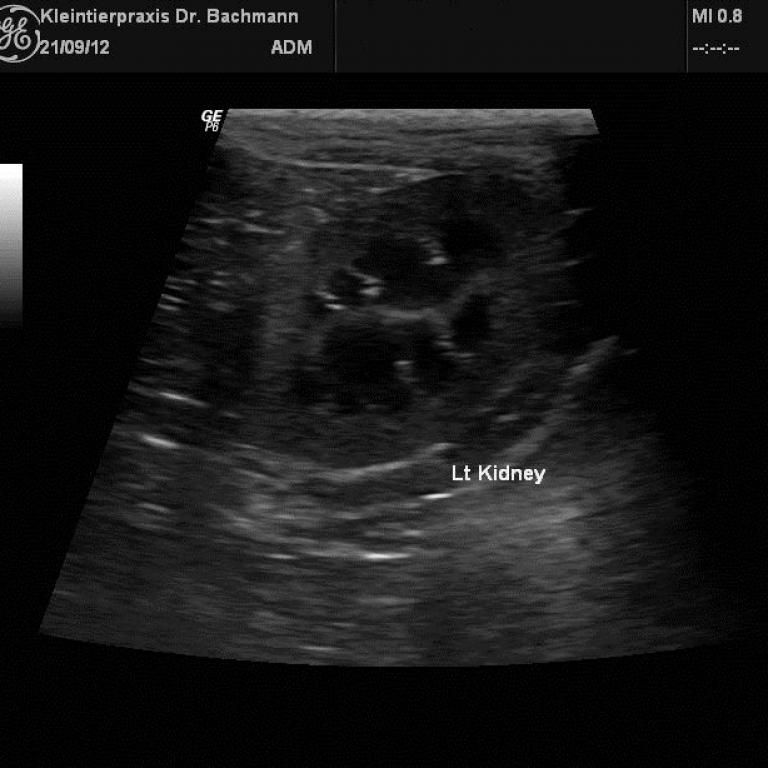

Eine leistungsstarke Röntgenanlage, ein modernes High-End-Ultraschallsystem und ein Videoendoskop ermöglichen uns ein breites Spektrum an bildgebender Diagnostik.